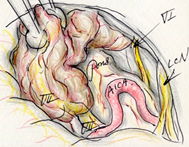

以下の画像に呈示するような脳幹や小脳を圧迫する大きい腫瘍に対しては、開頭手術が優先されます。手術中に神経刺激装置・聴性脳幹反応など電気生理学的モニタリングを併用し、1つ1つの手術操作によって神経機能を損傷していないか随時チェックしながら手術を行っており、術後後遺症の予防に努めています。